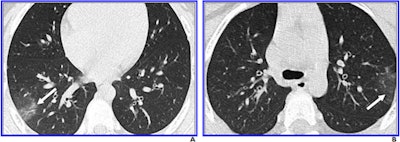

Steinberger and colleagues found that 77% of chest CT findings in the patient cohort were negative (23 of 30 children). Seven of the 30 patients had positive chest CT findings (as well as at least one clinical symptom on presentation); these findings were characterized by ground-glass opacities with peripheral distribution, the "crazy paving" pattern, and halo and reverse halo signs.

There were no pleural effusions or lymphadenopathy on chest CT in the patient cohort. Steinberger and colleagues noted that the severity of CT findings in the children increased with age. Of the 30 children, 11 (37%) underwent follow-up chest CT, and of those 11 exams, 10 (91%) showed no change.